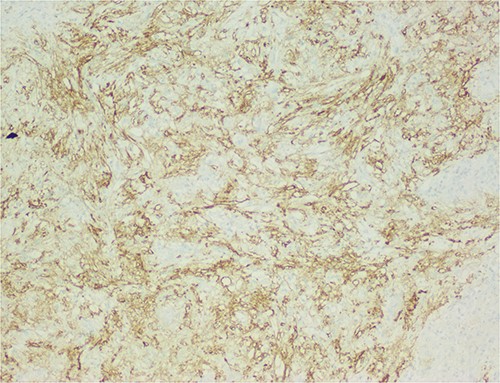

The histological evaluation of the surgical specimen revealed a storiform fusiform cell neoplasm with expansive borders, areas of a myopericytomatous pattern, and the presence of rhabdoid cells (Fig. 4). The neoplastic cells, spindled to oval, with eosinophilic and granular cytoplasm and with mild nuclear atypia, were organized in small bundles (Fig. 5). Anomalous arterial structures were observed. Neither necrosis nor mitotic figures were identified. The immunohistochemical study revealed immunoreactivity of neoplastic cells for SMA, HHF35 (Fig. 6) and HMB45 (Fig. 7), Calponin, S100 and CD31. The margins did not intersect the neoplasm. Thus, contrary to the preoperative diagnosis of hepatocellular carcinoma, the morphological aspects and the immunohistochemical profile favored the diagnosis of epithelioid angiomyolipoma.

Liver parenchyma partially occupied by a neoplastic proliferation with expansive borders.